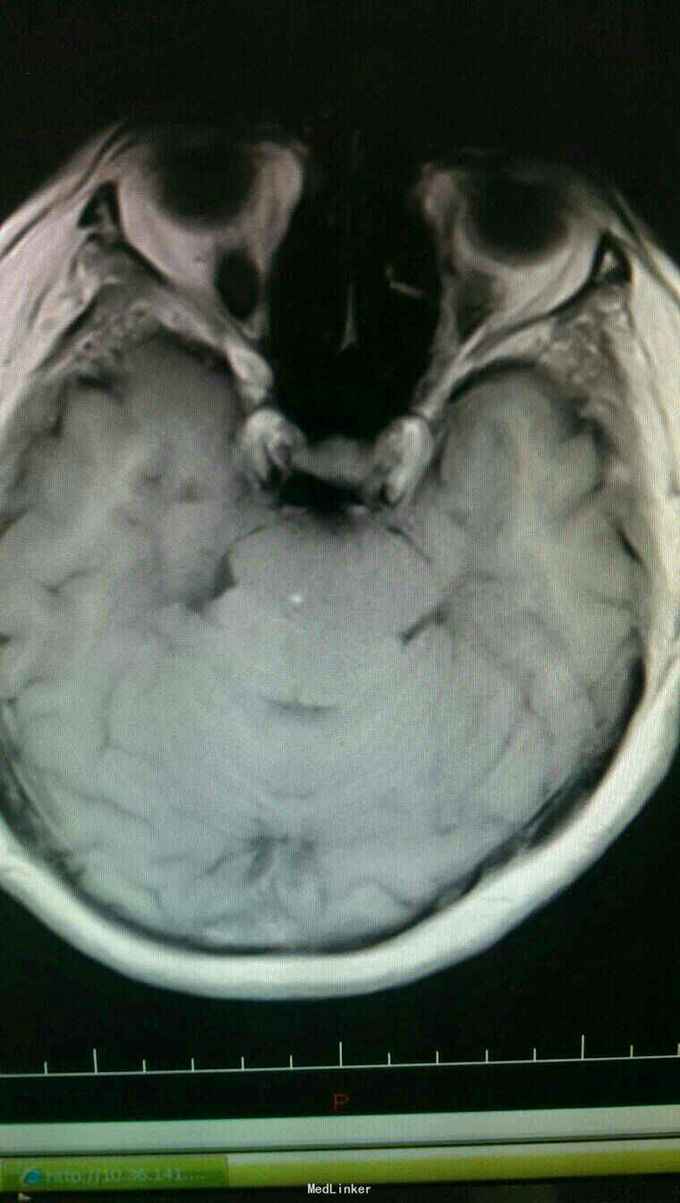

入院诊断:岩斜区脑膜瘤。完善术前准备,于全麻下行右侧颞下入路,岩斜区肿瘤切除,术中保留拉贝静脉,剪开小脑幕,近全切除肿瘤。

患者术后病情稳定,岩斜区位于颞骨岩部背面与枕骨斜坡部的岩斜裂汇合处,从岩骨尖至颈静脉孔。内侧至斜坡中线,外侧至第Ⅴ、Ⅶ和Ⅷ脑神经,上缘为鞍背,下缘为颈静脉孔水平;下方为枕骨大孔区。岩斜区脑膜瘤由于位置深,毗邻重要解剖结构,很难实现肿瘤全切除,且有较高的术后致残率,一直是神经外科手术的治疗难点。颅内脑膜瘤约0.3%~1.0%起源于岩斜区,是岩斜区最常见病变。它向上可侵犯岩骨尖、小脑幕、Meckel腔、鞍旁和海绵窦;向下侵犯内听道和颈静脉孔;向内侧达脑干和椎-基底动脉。当肿瘤很大时,可包绕同侧Ⅲ~Ⅺ脑神经。患者临床可表现头痛、复杂的脑神经麻痹、共济失调等症状,严重者表现为偏瘫、认知功能障碍。岩斜区脑膜瘤多数表现良性过程,目前,仍以手术切除为首选治疗方式。 岩斜区脑膜瘤手术技术非常关键,需要熟悉岩斜区解剖关系并有丰富的显微操作经验。在术前放置腰穿引流,或术中甘露醇应用可明显降低脑组织压力,减少牵拉造成的副损伤。提前对脑膜瘤基底的处理可有效避免肿瘤持续出血造成的蛛网膜界面消失。肿瘤的生长将神经、血管拉伸或包绕,尤其是复发的肿瘤,会破坏蛛网膜界面,侵犯脑干软脑膜。手术时应仔细分辨和保护。肿瘤囊壁与神经、血管外膜和脑干粘连,不应勉强分离,以保护下方结构。 待术后平稳复查头Ct。